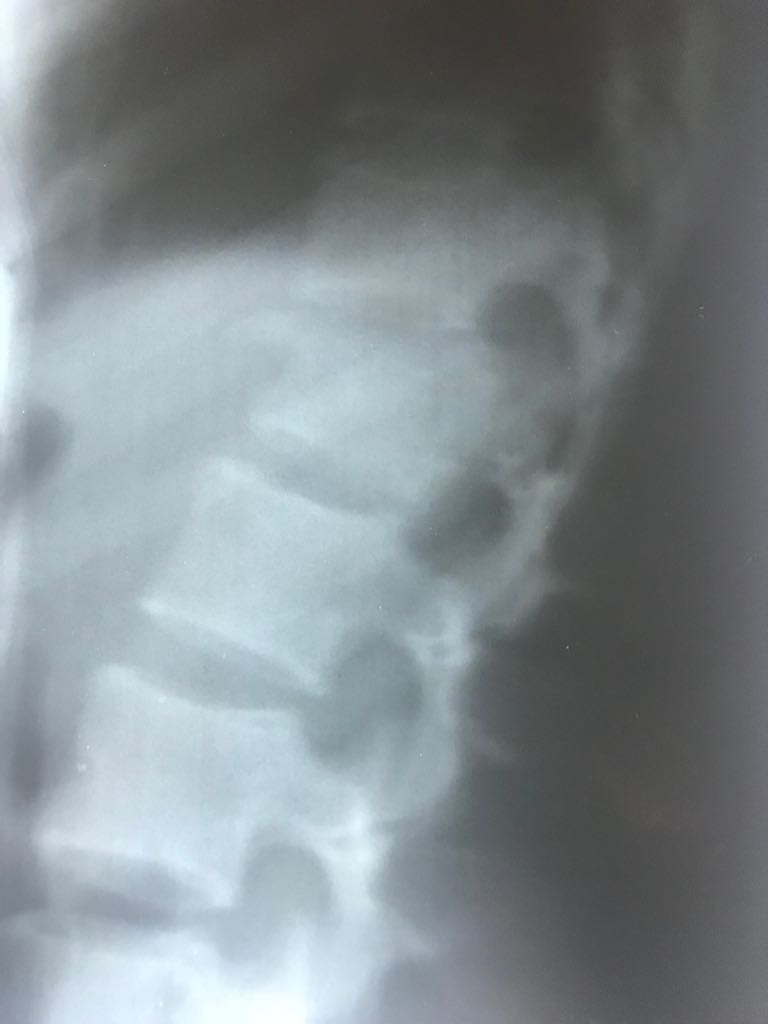

Ameliyat Öncesi